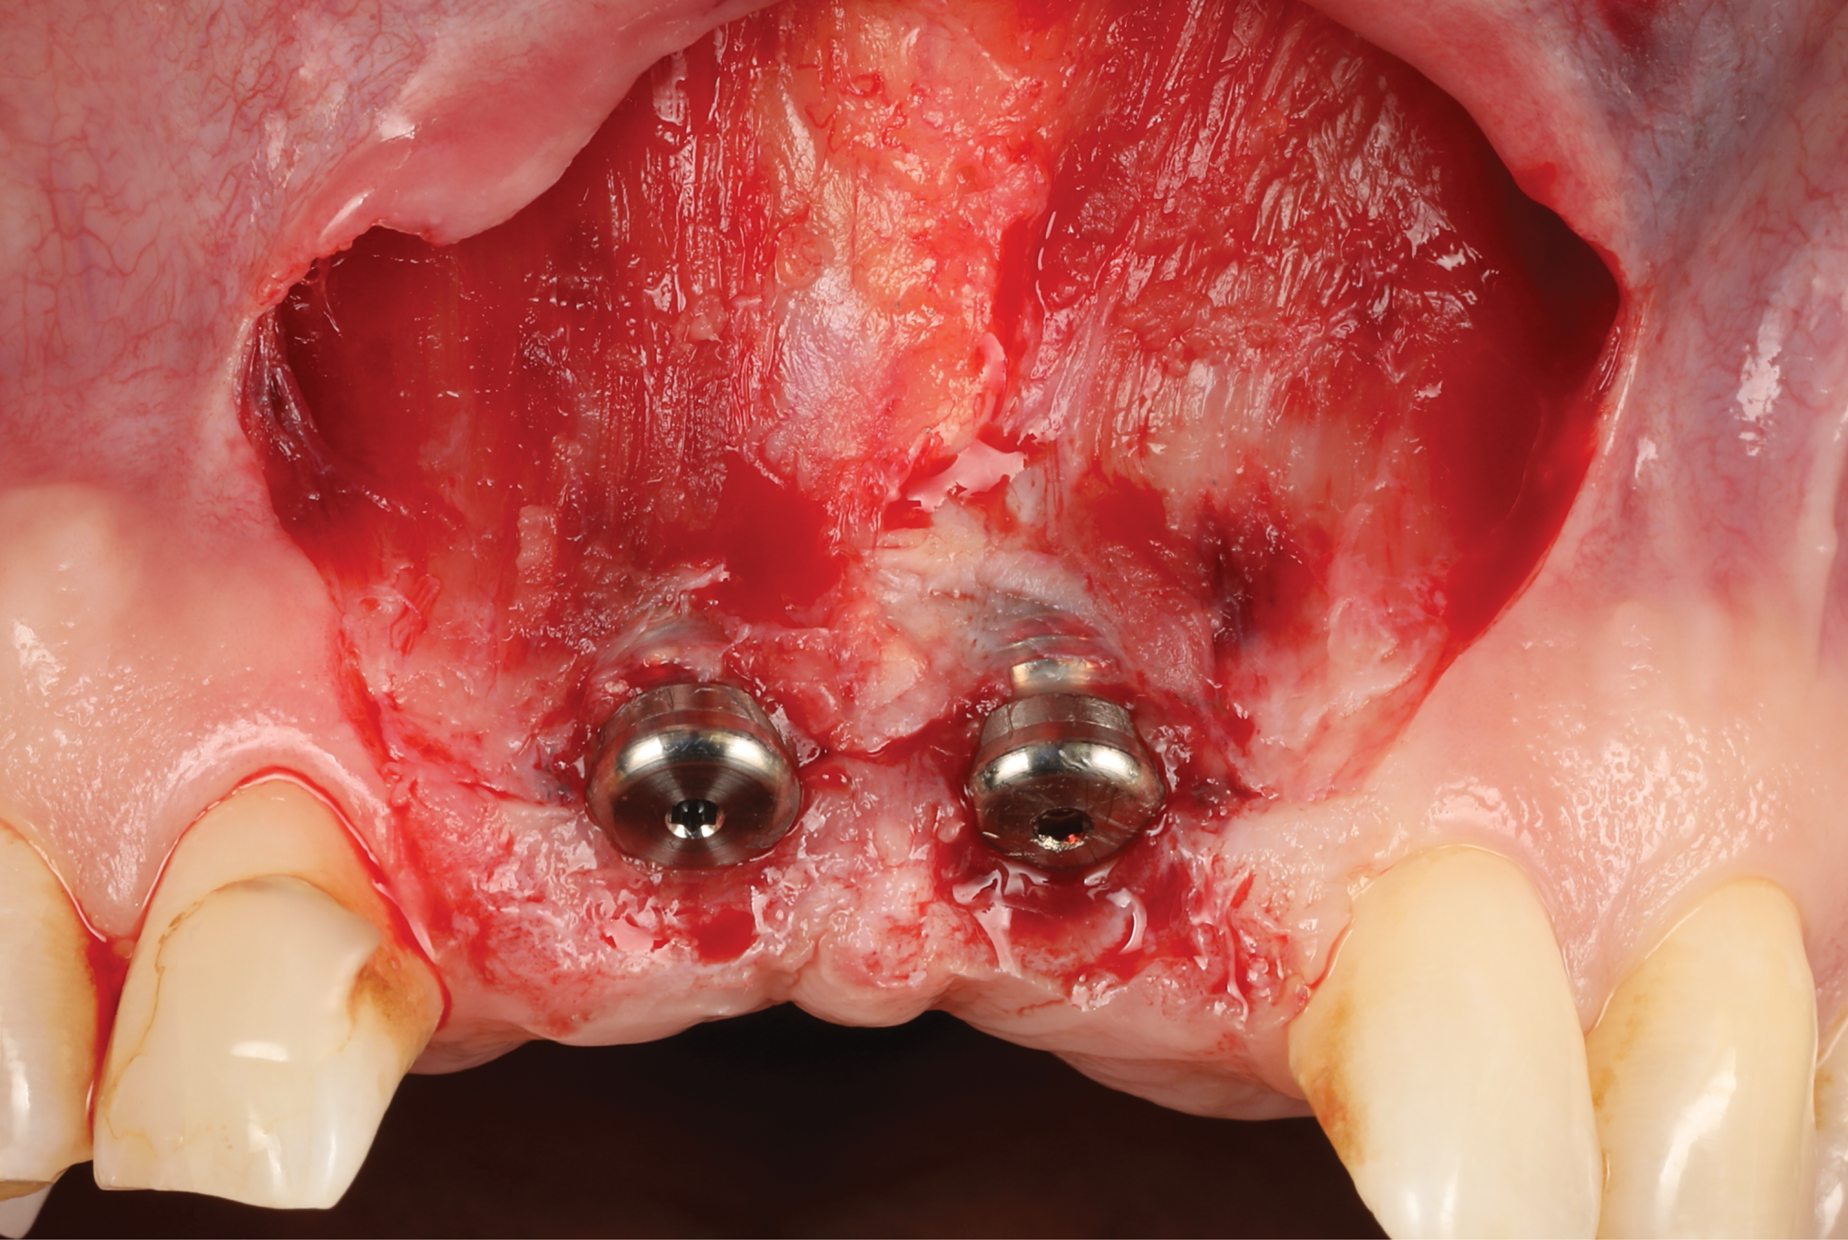

Oral hygiene instructions were reviewed with the patient and reinforced 6 weeks before the surgical visit. At the surgical appointment, the implant-supported crowns and abutments were removed, and two cover screws were inserted. A split-thickness trapezoidal-shape CAF was performed (Figure 3). The two slightly divergent beveled oblique incisions were placed between the implants and lateral incisors. A split-thickness flap was elevated, with meticulous care taken to maintain a layer of connective tissue adherent to the implant surface. Maintaining this layer of connective tissue on the implant body lacking buccal bone is an important step that differentiates flap elevation on healthy implants with PSTDs from implants with peri-implantitis (Figure 4).

Fig 3. Coronally advanced flap after removal of the crowns for soft-tissue augmentation.

Figure 3